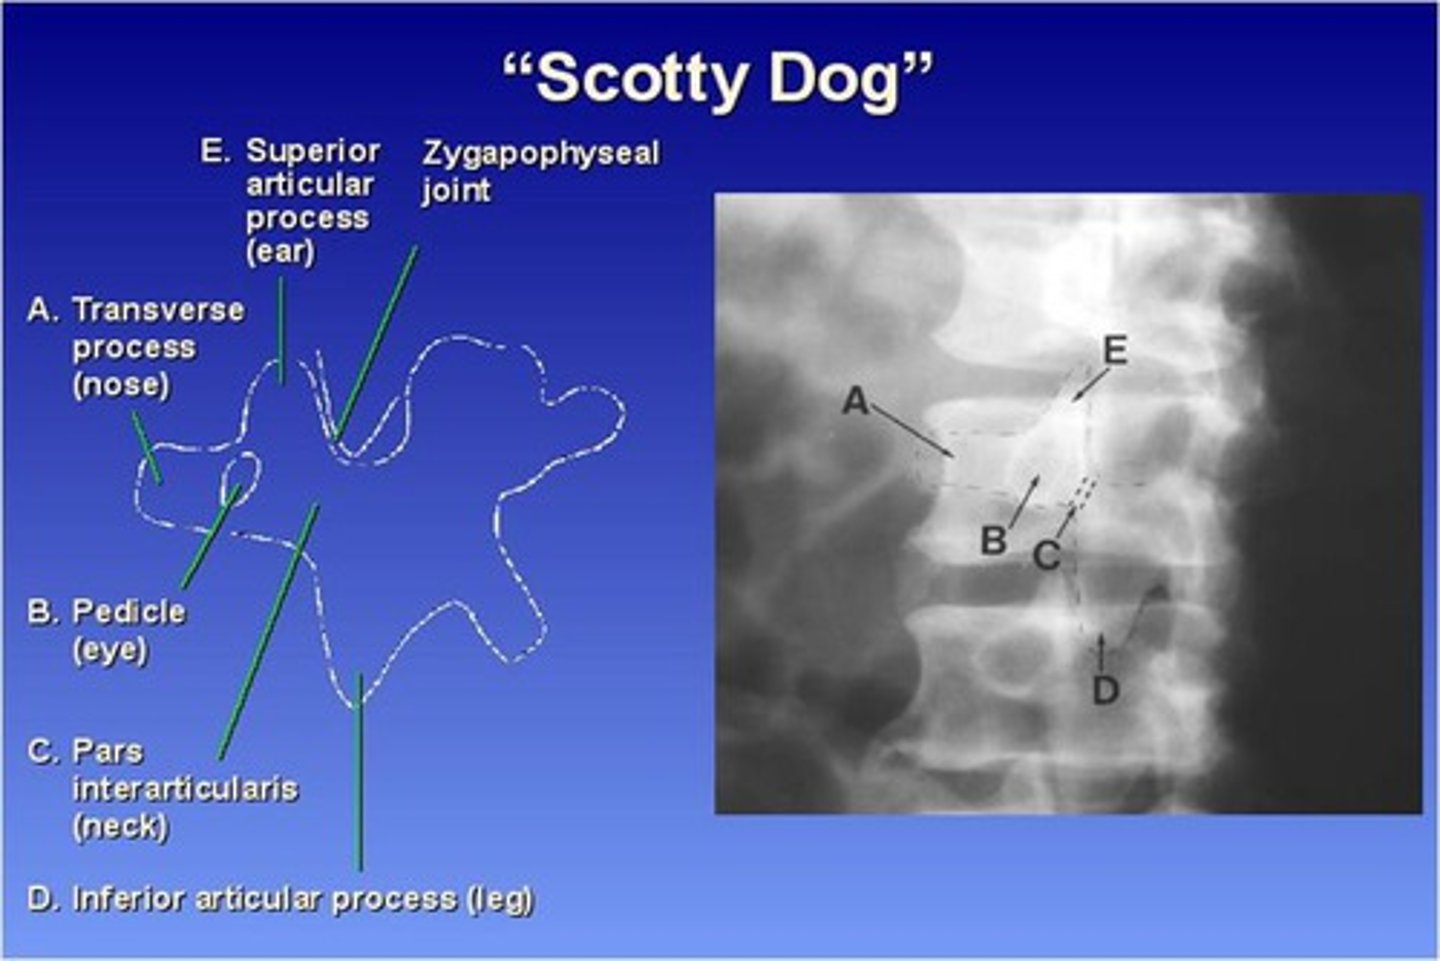

The Lumbar zygapophyseal joints are ONLY demonstrated on what view?

45 degree obliques (will see "scotty dog")

What part of the lumbar spine makes up the "nose" of the "scotty dog"?

transverse process

What part of the lumbar spine makes up the "eye" of the "scotty dog"?

pedicle

What part of the lumbar spine makes up the "neck" of the "scotty dog"?

pars interarticularis

What is the pars interarticularis?

portion of each lamina between the superior and inferior articular processes

What part of the lumbar spine makes up the "leg" of the "scotty dog"?

inferior articular process

What part of the lumbar spine makes up the "ear" of the "scotty dog"?

superior articular process